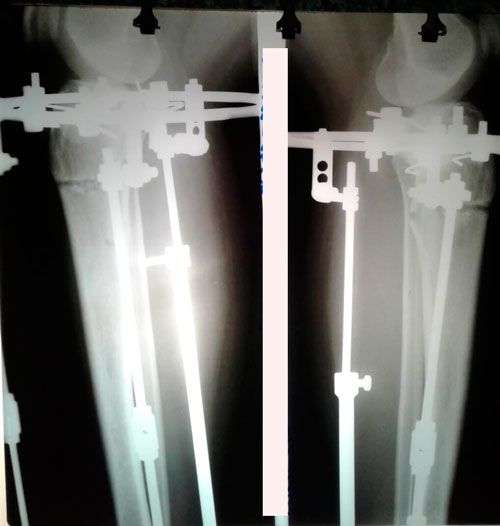

Дата операции - 05.03.2019г.

Дата снятия аппаратов - 26.06.2019г.

Срок сращения - 110 дней.